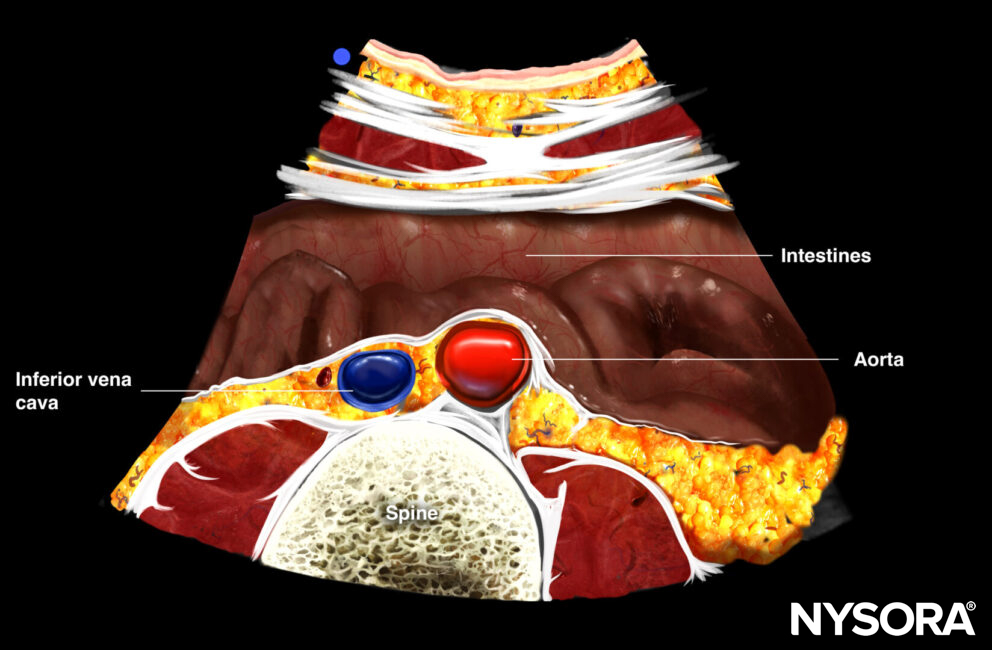

- Always distinguish the aorta from the inferior vena cava (IVC)

- Due to its close proximity to the aorta and the regular respiratory cycle, the IVC may mimic the aorta, pulsating with each breath. However, pulsed wave Doppler easily distinguishes the aorta’s pulsatile flow from the IVC’s venous flow.

Differences between the aorta and IVC.

- Identify the aorta, IVC, and the vertebral body with its acoustic shadow. Adjust depth if needed to identify these 3 structures.